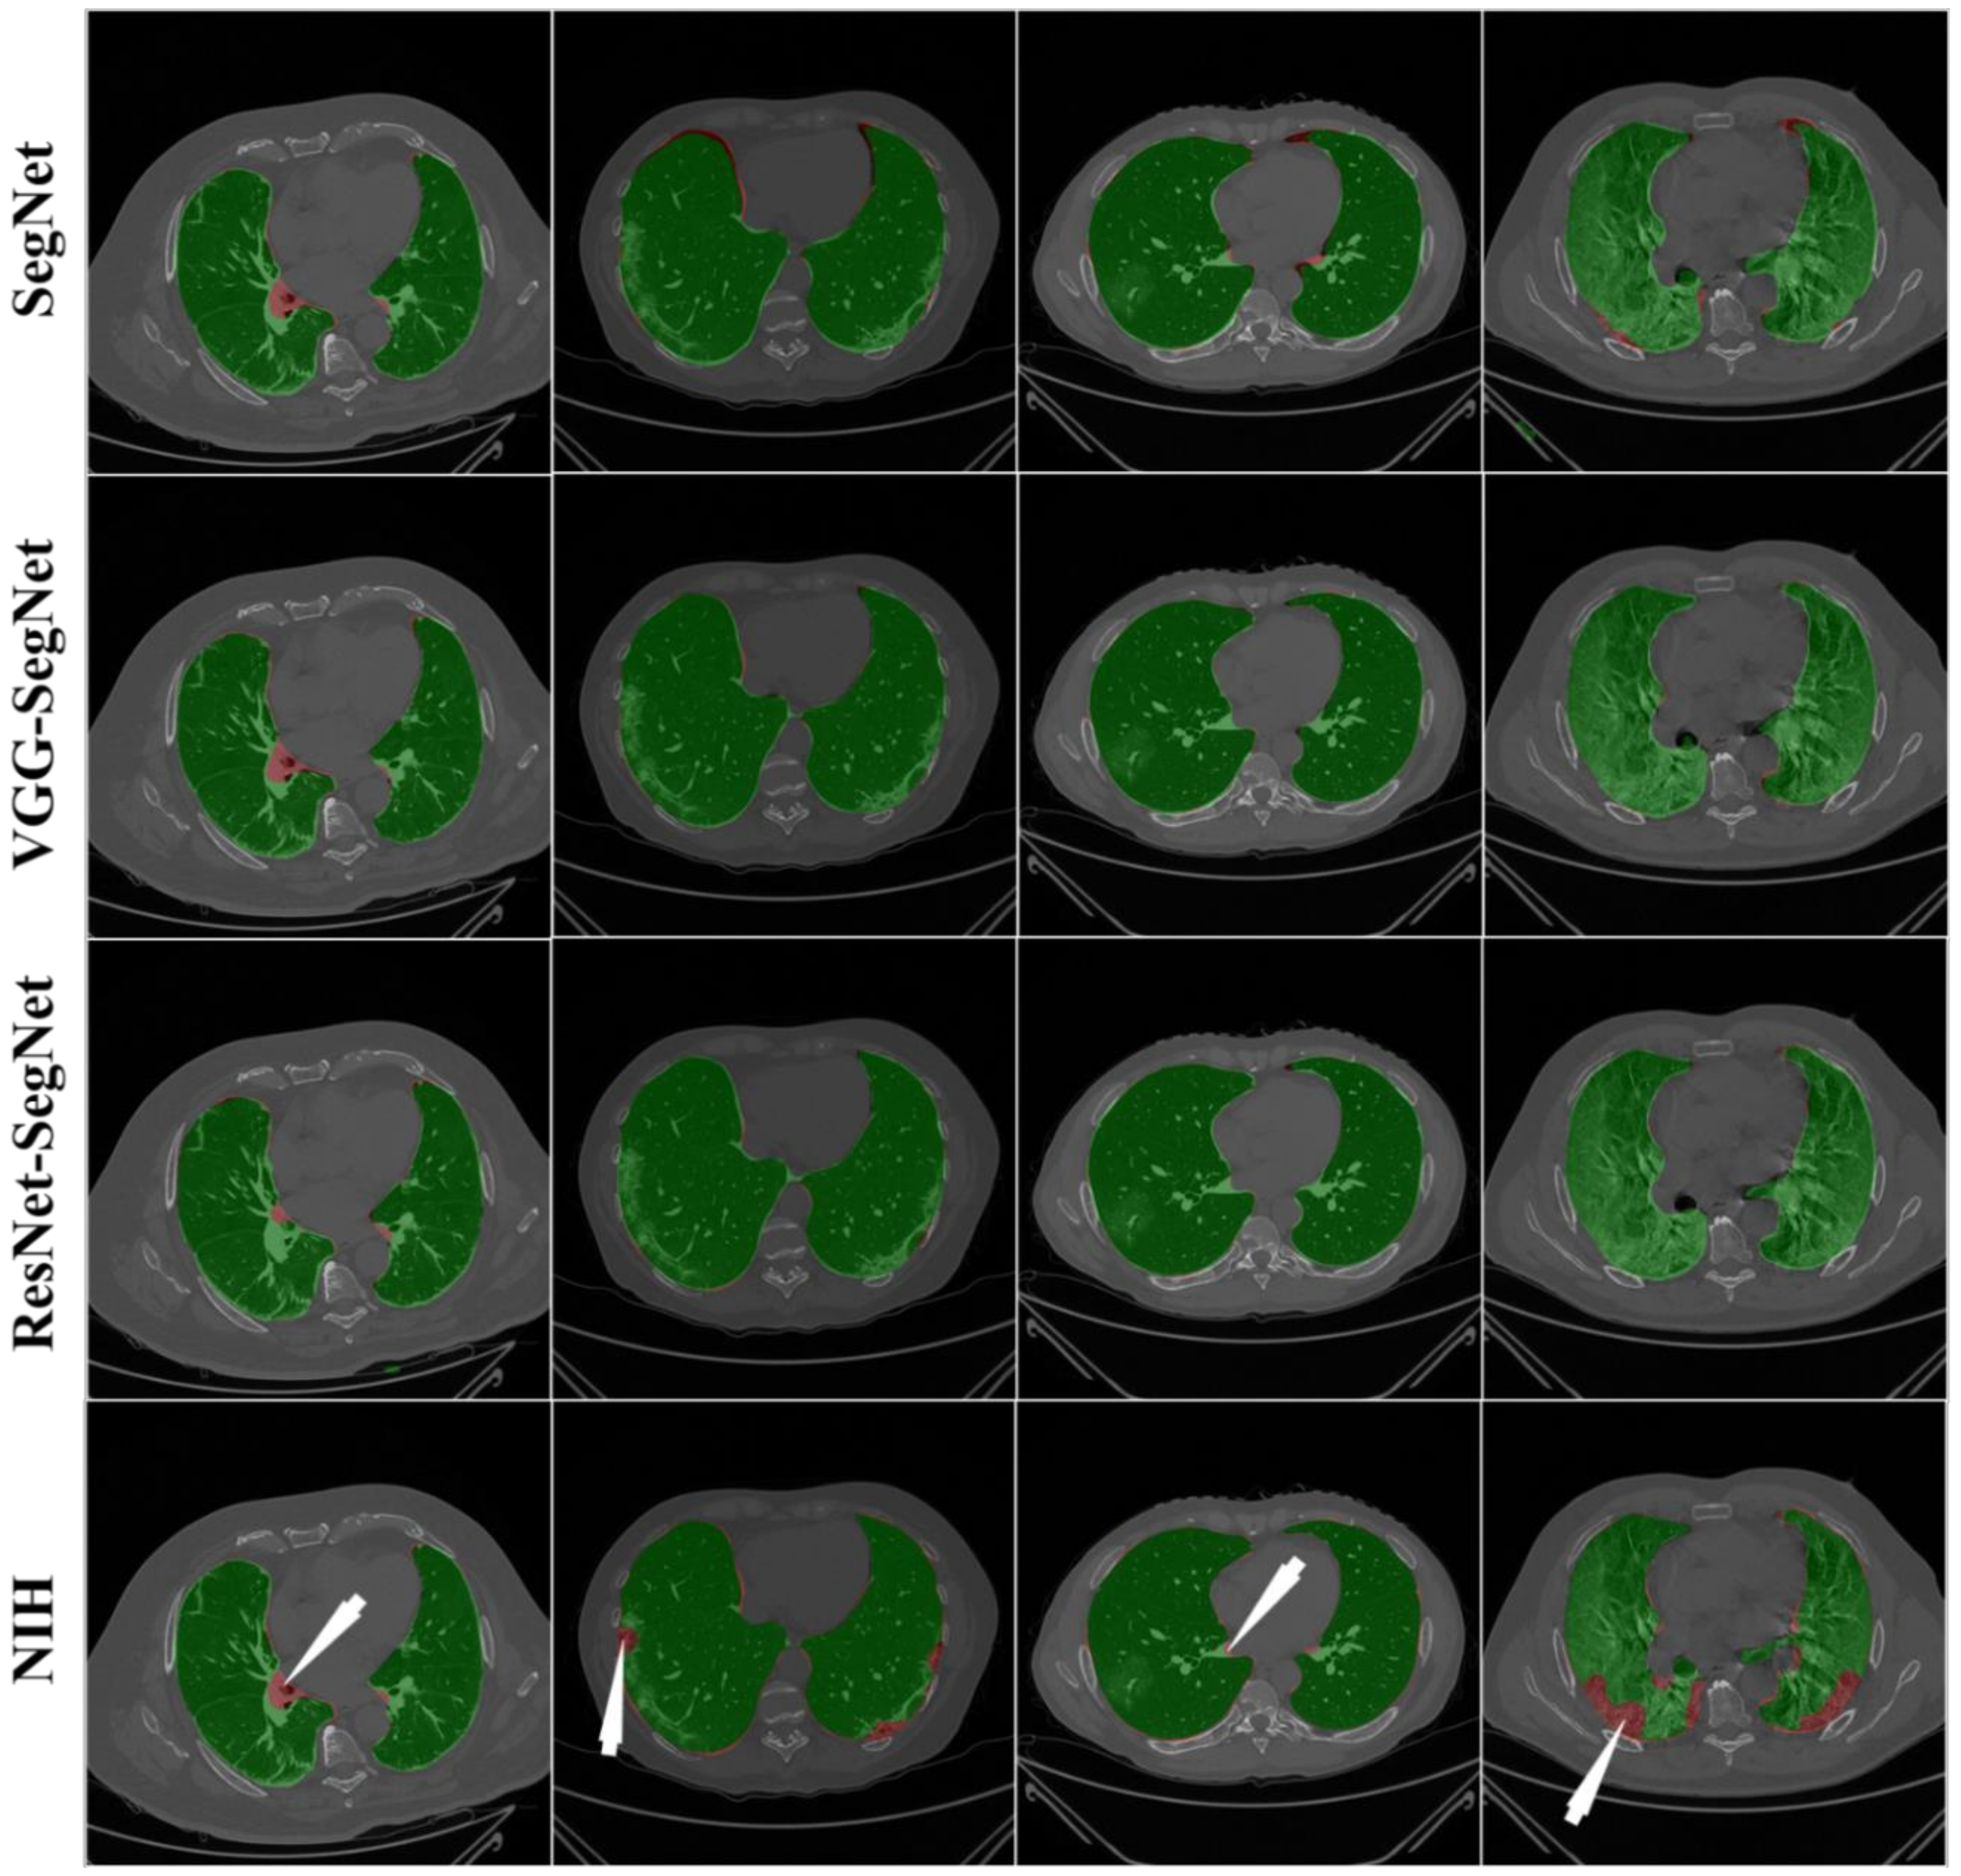

4.2.1. Visualization of Lung Boundary and Regional Lung Error

4.2.2. Performance Metrics for the Lung Area Error